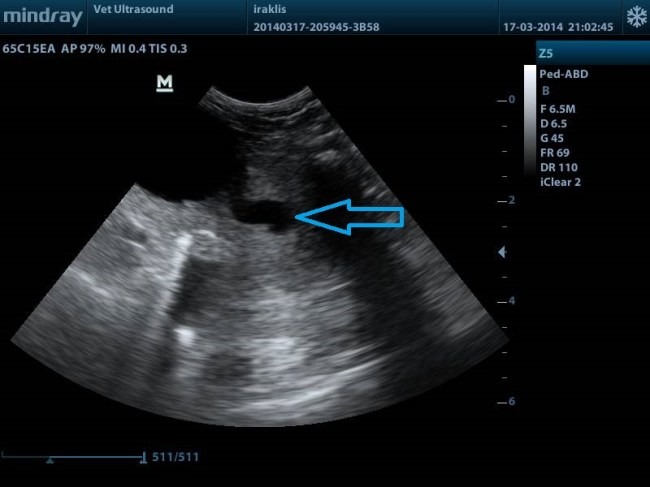

ΤΟ ΜΠΛΕ ΒΕΛΟΣ ΔΕΙΧΝΕΙ ΤΗΝ ΔΙΑΤΑΣΗ ΤΟΥ ΕΝΔΟΠΡΟΣΤΑΤΙΚΟΥ ΤΜΗΜΑΤΟΣ ΤΗΣ ΟΥΡΗΘΡΑΣ.